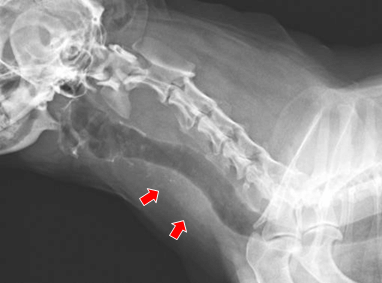

【実施症例】甲状腺癌に対する動注療法

ミニチュア・ダックスフンド、12歳、雌。

周囲組織に浸潤した甲状腺癌で外科的切除は困難であった。 大腿動脈からカテーテルを挿入し、腫瘍栄養血管である甲状腺動脈に抗がん剤と塞栓物質の選択的注入を行った。 実施後、腫瘍は縮小し症状の改善が得られた。

実施前のX線像(腫瘍が気管を圧迫)

実施前のX線像

(腫瘍が気管を圧迫)

実施後のX線像(腫瘍が縮小し気管の圧迫が改善)

実施後のX線像

(腫瘍が縮小し

気管の圧迫が改善)